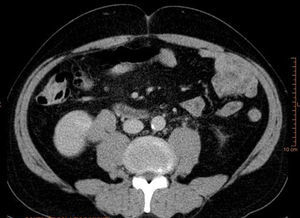

En la TAC aportada se apreciaba una ectasia pieloureteral derecha grado ii/iv, producida por una lesión polipoidea en la pelvis renal que se extendía al uréter proximal, así como lesiones hepáticas (figs. 1-3). La citología urinaria era negativa para células neoplásicas, y la cistoscopia no reveló la presencia de lesión vesical concominante.